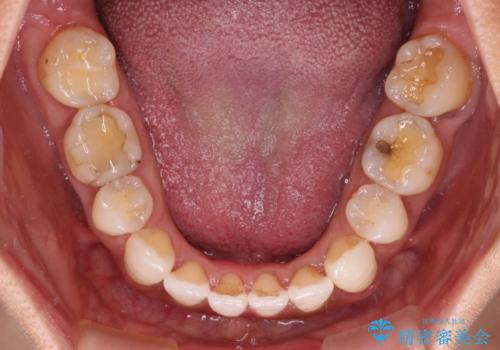

- 下顎前歯を中心に、以前行った矯正治療の後戻りが気になるとのことで来院された患者様です。

後戻りは軽度であったため、インビザライン・ライトにて治療を行うこととしました。

矯正治療後は、再度後戻りすることを極力回避するために、下顎前歯の舌側を細いワイヤーを用いて保定することとしました。